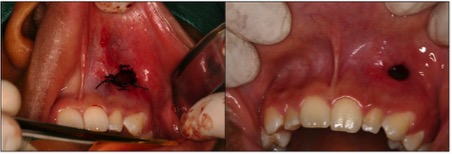

Dens in dente is a dental development malformation that involves more commonly the upper lateral incisors. Infection of the canal of these teeth can cause the formation of chronic periapical lesions. The present study aimed to describe an integrated approach between the endodontic therapy and surgical intervention in an upper lateral incisor with dens in dente type II. A female patient, 14 years old, looked for dental care complaining of left palatal and paranasal bulging. Clinical, radiological and histopathological findings suggested periradicular cyst. First, marsupialization was performed to reduce the size of the lesion and to favor its enucleation, with less risk of injuring the tooth and vital structures. After diagnosis of pulp necrosis and in attempt to reduce the infection via canal, we used the reciprocating instrumentation associated with irrigation with sodium hypochlorite, intracanal medication based on calcium hydroxide and filled with a thermoplastic filling. After a year of marsupialization, fistulectomy and complete enucleation of the lesion were performed. Proservation was performed 1, 3, 6 and 12 months following marsupialization. Six months after enucleation, we observed the periradicular repair and remission of symptoms. The extensive apical lesion associated with dens in dente type II can be treated with a combination of surgical and endodontic therapy.